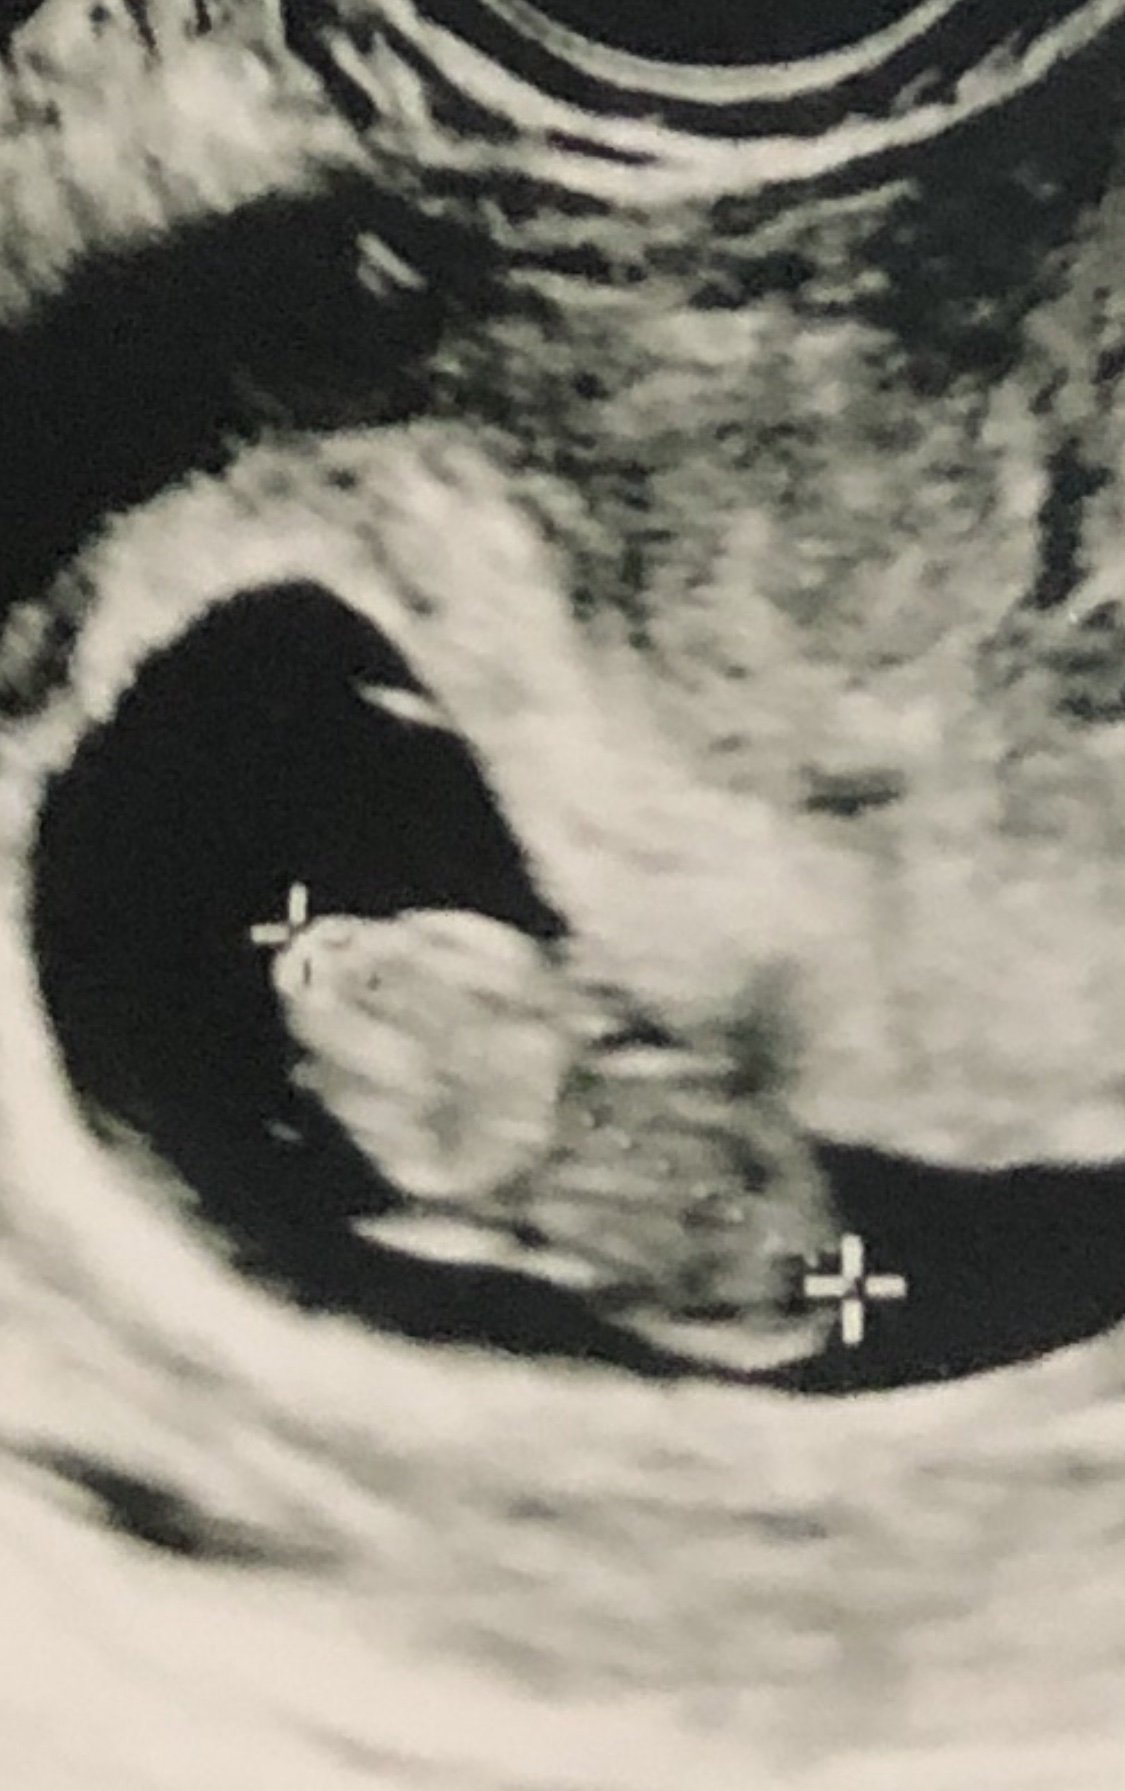

Jan 19 2018 - Fresh Transfer #1 one 5dt; BFP 1/25/2018; EDD 10/7/2018; MMC at 8w3d; D&C 3/6/2018

Well No more PIO for this girl!!! Graduated from my RE today 😊 little man is looking great! Next stop OB on 12/18!

I just had my first OB appointment today--definitely a different experience. Took vitals, 6 vials of blood, and urine. Then i had an U/S but i didn't get print out!? Maybe i should have asked for a copy--but it seems like it would be a no brainer. I didn't push it b/c the images weren't as nice as the ones i had from the RE but still. HR was 171 so that was nice to know.